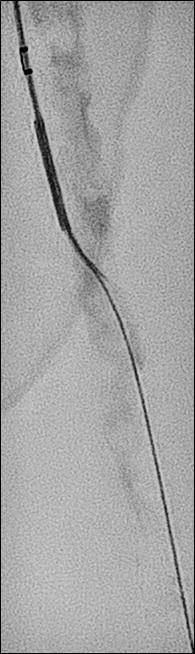

n PERIPHERAL ARTERIAL DISEASE:

Crossing chronic total occlusion lesions are challenging procedures. The BeBack crossing catheter—Bentley’s first product to be available in both Europe and the USA following the company’s acquisition of Upstream Peripheral Medical Technologies’ GoBack crossing catheter in September 2022— offers a new solution in this space. In a Bentleysponsored advertorial, Andrej Schmidt (Leipzig, Germany) shares his clinical experience with the BeBack, noting how it has been a “gamechanger” in his endovascular peripheral arterial disease practice.

For more on this story go to page 19.